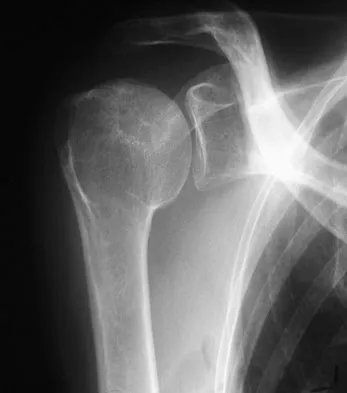

A 58-year-old woman with a history of severe asthma and long-term prednisone use reports a progression of chronic shoulder pain for the past 6 months. Radiographs and MRI scans are shown in Figures 30a through 30d. What is the most likely diagnosis?

The patient has osteonecrosis of the humeral head. The radiographs show increased density in the superior subchondral region of the humeral head. The MRI scans reveal a central collapse of the humeral head. The patient's history of severe asthma and long-term prednisone use predisposes her to this condition. The MRI scans show no evidence of a full- or partial-thickness rotator cuff tear. Without a history of fevers, chills, or other systemic signs or symptoms, there is no indication of septic arthritis. The radiographs do not reveal periarticular erosions, commonly seen in rheumatoid arthritis. Matsen FA III, Rockwood CA Jr, Wirth MA, et al: Glenohumeral arthritis and its management, in Rockwood CA Jr, Matsen FA III (eds): Rockwood and Matsen The Shoulder, ed 2. Philadelphia, PA, WB Saunders, 1998, pp 871-874.